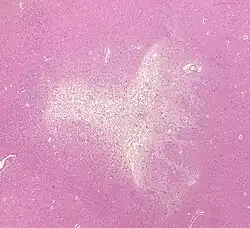

Much of the current knowledge of lacunar strokes comes from C. Miller Fisher's cadaver dissections of post-mortem stroke patients. He observed "lacunae" (empty spaces) in the deep brain structures after occlusion of 200–800 μm penetrating arteries and connected them with five classic syndromes. These syndromes are still noted today, though lacunar infarcts are diagnosed based on clinical judgment and radiologic imaging.